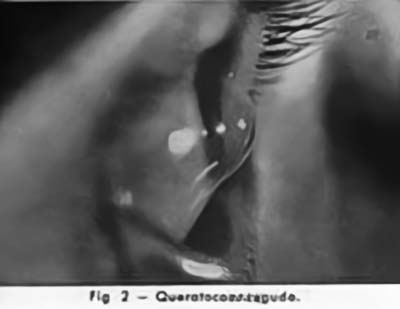

La Cirugía Laminar Refractiva conocida hoy con los nombres de LASIK, PRK, LASEK, se inició a mediados del siglo XX, cuando tratando de solucionar los problemas de visión de los pacientes con Queratocono un oftalmólogo el Dr José I. Barraquer Moner, pudo observar la gran disminución del defecto miópico que padecían, despues realizar sobre los grandes conos un injerto de córnea laminar de 12 mm de diámetro. La aplanación subsecuente de la córnea generaba el cambio refractivo